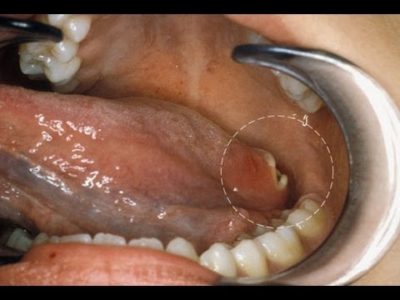

Oral cancer

Cancer is defined as the uncontrollable growth of cells that invade and cause damage to surrounding tissue. Oral cancer appears as a... Learn More

Warning signs of oral cancer – Dr. Shyam Padmanabhan

Oral cancers can occur in any part of the oral cavity. This could include the lips, the tongue, the throat, the pharynx,... Learn More